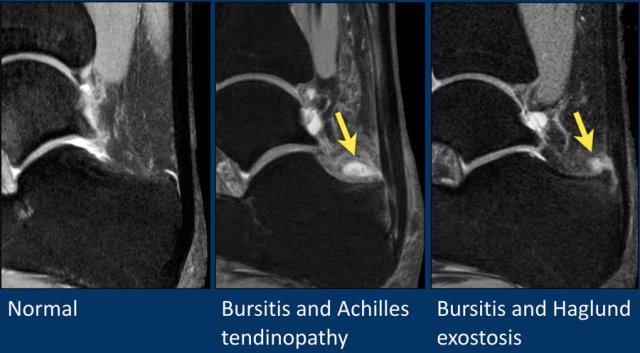

Normally, a small amount of fluid is seen in the retrocalcanear bursa.

Too much fluid is indicative of bursitis.

Thickening of the Achilles is seen with paratenonitis.

The Haglund syndrome consists of the triad of:

1. Haglunds exostosis

2. Retrocalcaneal bursitis

3. Achilles insertional tendinopathy